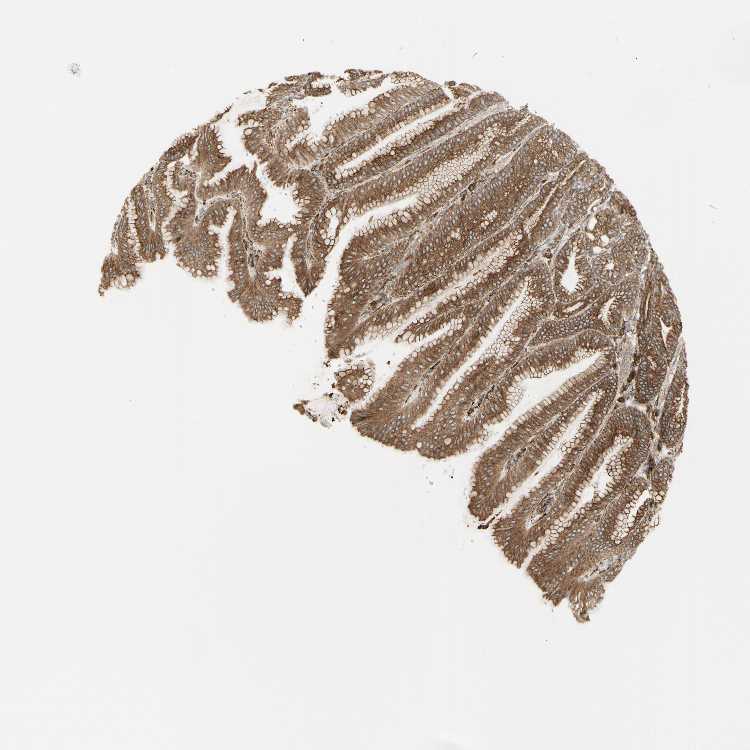

STOMACH 1 - Antibody stainingi

Antibody staining in the annotated cell types in the current human tissue is reported as not detected, low, medium, or high, based on conventional immunohistochemistry profiling in selected tissues. This score is based on the combination of the staining intensity and fraction of stained cells.

Each image is clickable and will lead to virtual microscopy that enables deeper exploration of all samples and also displays staining intensity scores, fraction scores and subcellular localization as well as patient and tissue information for each sample.

Antibody HPA009433Antibody HPA009696Antibody CAB004738

Glandular cells HighHighHigh